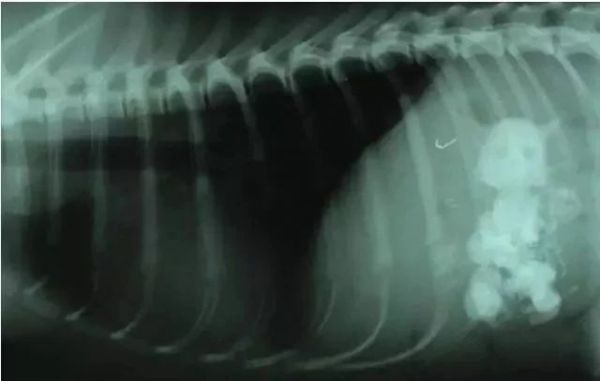

偷吃戒指、偷吃奶嘴还不是最厉害的。你能想象这只狗一共吞下了109颗石子吗!

有宠物医院专门PO出了一些X光影像来提醒铲屎官注意狗狗异食行为,看看它们吞下的东西简直让人瞠目结舌。